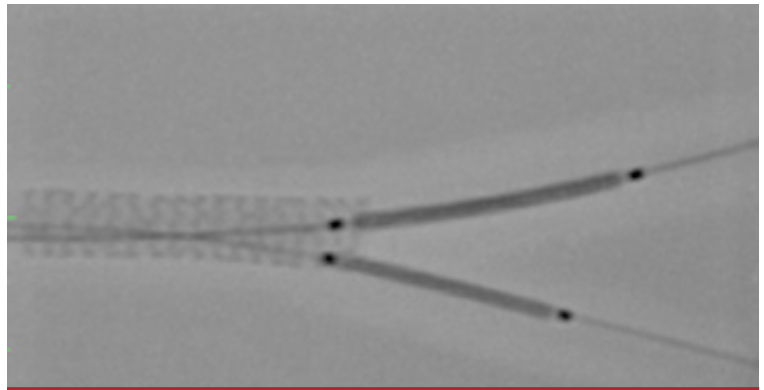

4. Using the jailed SB guidewire for guidance, advance a new guidewire through and out the distal lumen of the deployed MV stent into the SB, taking care not to catch a stent strut (Figure 4). Remove the jailed SB wire to avoid trapping and fracture of the distal tip. Postdilate the MV stent using a noncompliant balloon to ensure that the lesion and stent are fully expanded and the stent is optimally opposed to the vessel wall (Figure 5).

b. Medina 1,1,0 or 1,0,1. A stent with its diameter and length matched to the downstream MV/SB vessel and disease is positioned with its proximal edge abutting the upstream MV stent, and a noncompliant balloon is positioned in the SB or distal MV (Figure 6). Image-enhancement software, such as CLEARstent (Siemens) or StentBoost (Philips), is useful for ensuring exact positioning of the stent. The stent is deployed, the delivery balloon is withdrawn 1-2 mm, and kissing-balloon inflation is performed.

c. Medina 1,1,1. Two appropriately sized stents can be positioned in the downstream MV and SB, respectively, and deployed simultaneously (Figure 7). Both stent delivery balloons are then withdrawn 1-2 mm and postdilation is performed (Figure 8). With some stent types, 2 devices cannot be simultaneously advanced through a 6-Fr guide catheter. In those circumstances, a 7-Fr guide (or a 7.5-Fr sheathless guide catheter) can be used. Alternatively, 1 stent is deployed with a balloon in the other vessel, as for a provisional approach, followed by another stent and balloon, in the nonstented and stented vessels, respectively. This completes the full PD Y-stent technique using 3 stents (Figure 9).